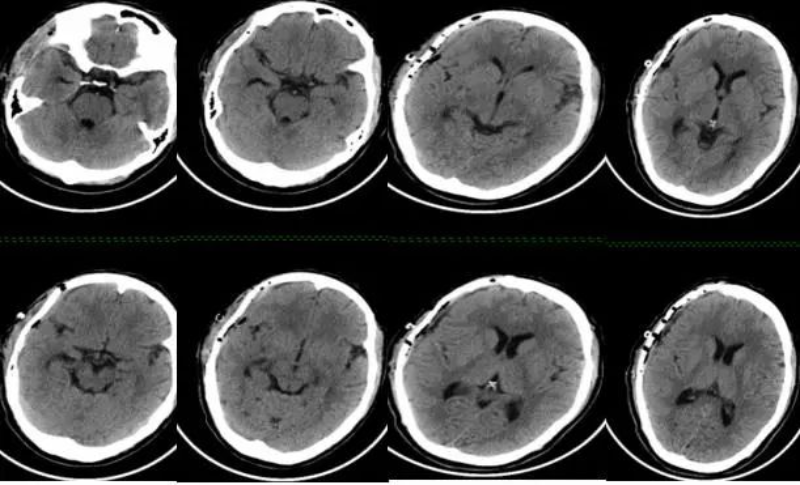

六个月后的10月20日,王女士步行来我院,住院并要求行“右额颞顶部颅骨缺损修补术”,黄小山主任再次组织麻醉科、肾内科、心血管内科进行术前讨论。10月29日,由黄小山主刀成功为王女士实施了右额颞顶部颅骨缺损修补术。至此,患者的治疗画上了圆满的句号。

△ 颅骨修补术后CT。